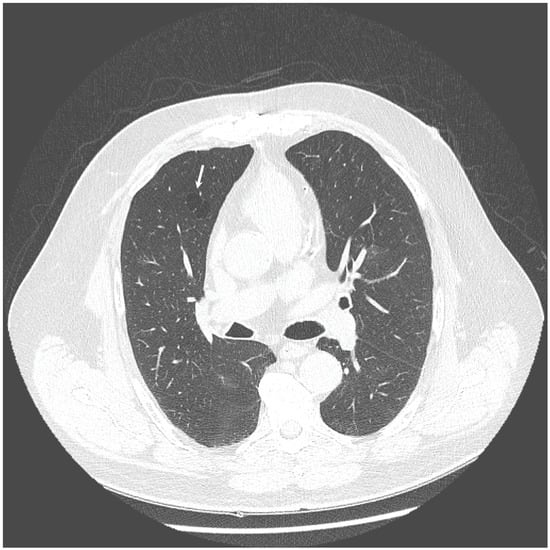

The chest X-ray showed linear opacities in the lower right lobe due to atelectasis, comparable to the previous examination results. The high-resolution computed tomography confirmed emphysema features and revealed thickening of bronchial walls with secretions accumulation and slight post-inflammatory changes (Figure 1 and Figure 2). No features of bronchiectasis nor enlarged lymph nodes in mediastinum and hilar space were present, and no fluid signs in the pleura.

Figure 2. HRCT scan—Secretions accumulation and slight post-inflammatory changes (indicated by the white arrows).